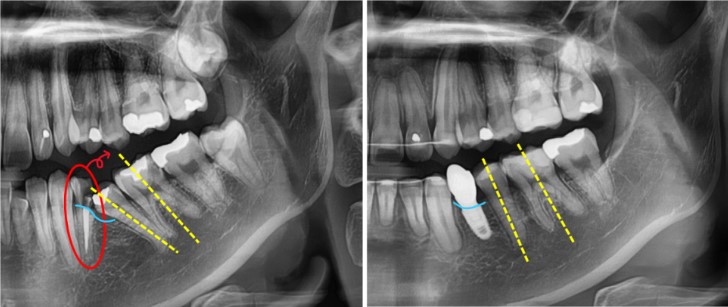

아래 증례는

신경치료한 치아가 깊숙이 깨져 발치 후 임플란트가 필요한 상태에서

먼저 쓰러져 있던 어금니들을 교정으로 세워주고

마지막 단계에 임플란트를 식립한 경우입니다.

치아가 곧게 서면서 잇몸뼈 높이도 더 좋아져임플란트를 심기에 이상적인 환경이 형성되었습니다.